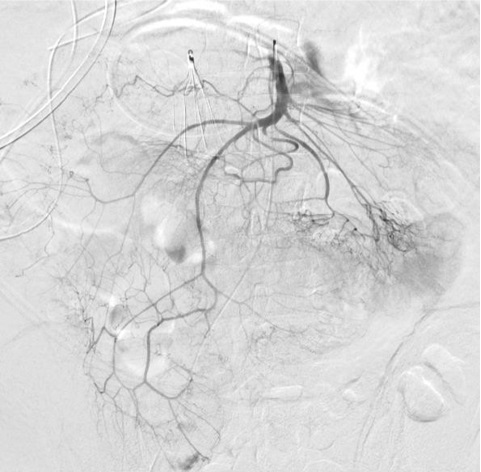

无论如何高质量动脉造影图像(DSA)的获取是下消化道出血栓塞的关键因素▲ 导管位置固定 Have catheter well seated,在注射造影剂情况下,有时导管会向后撤 ▲ 注射足够的造影剂 Inject enough contrast

▲ 选择性血管分支注射 Inject selectively,例如肠系膜分支的选择性造影可以提高阳性率

选择性分支注射的价值(1)